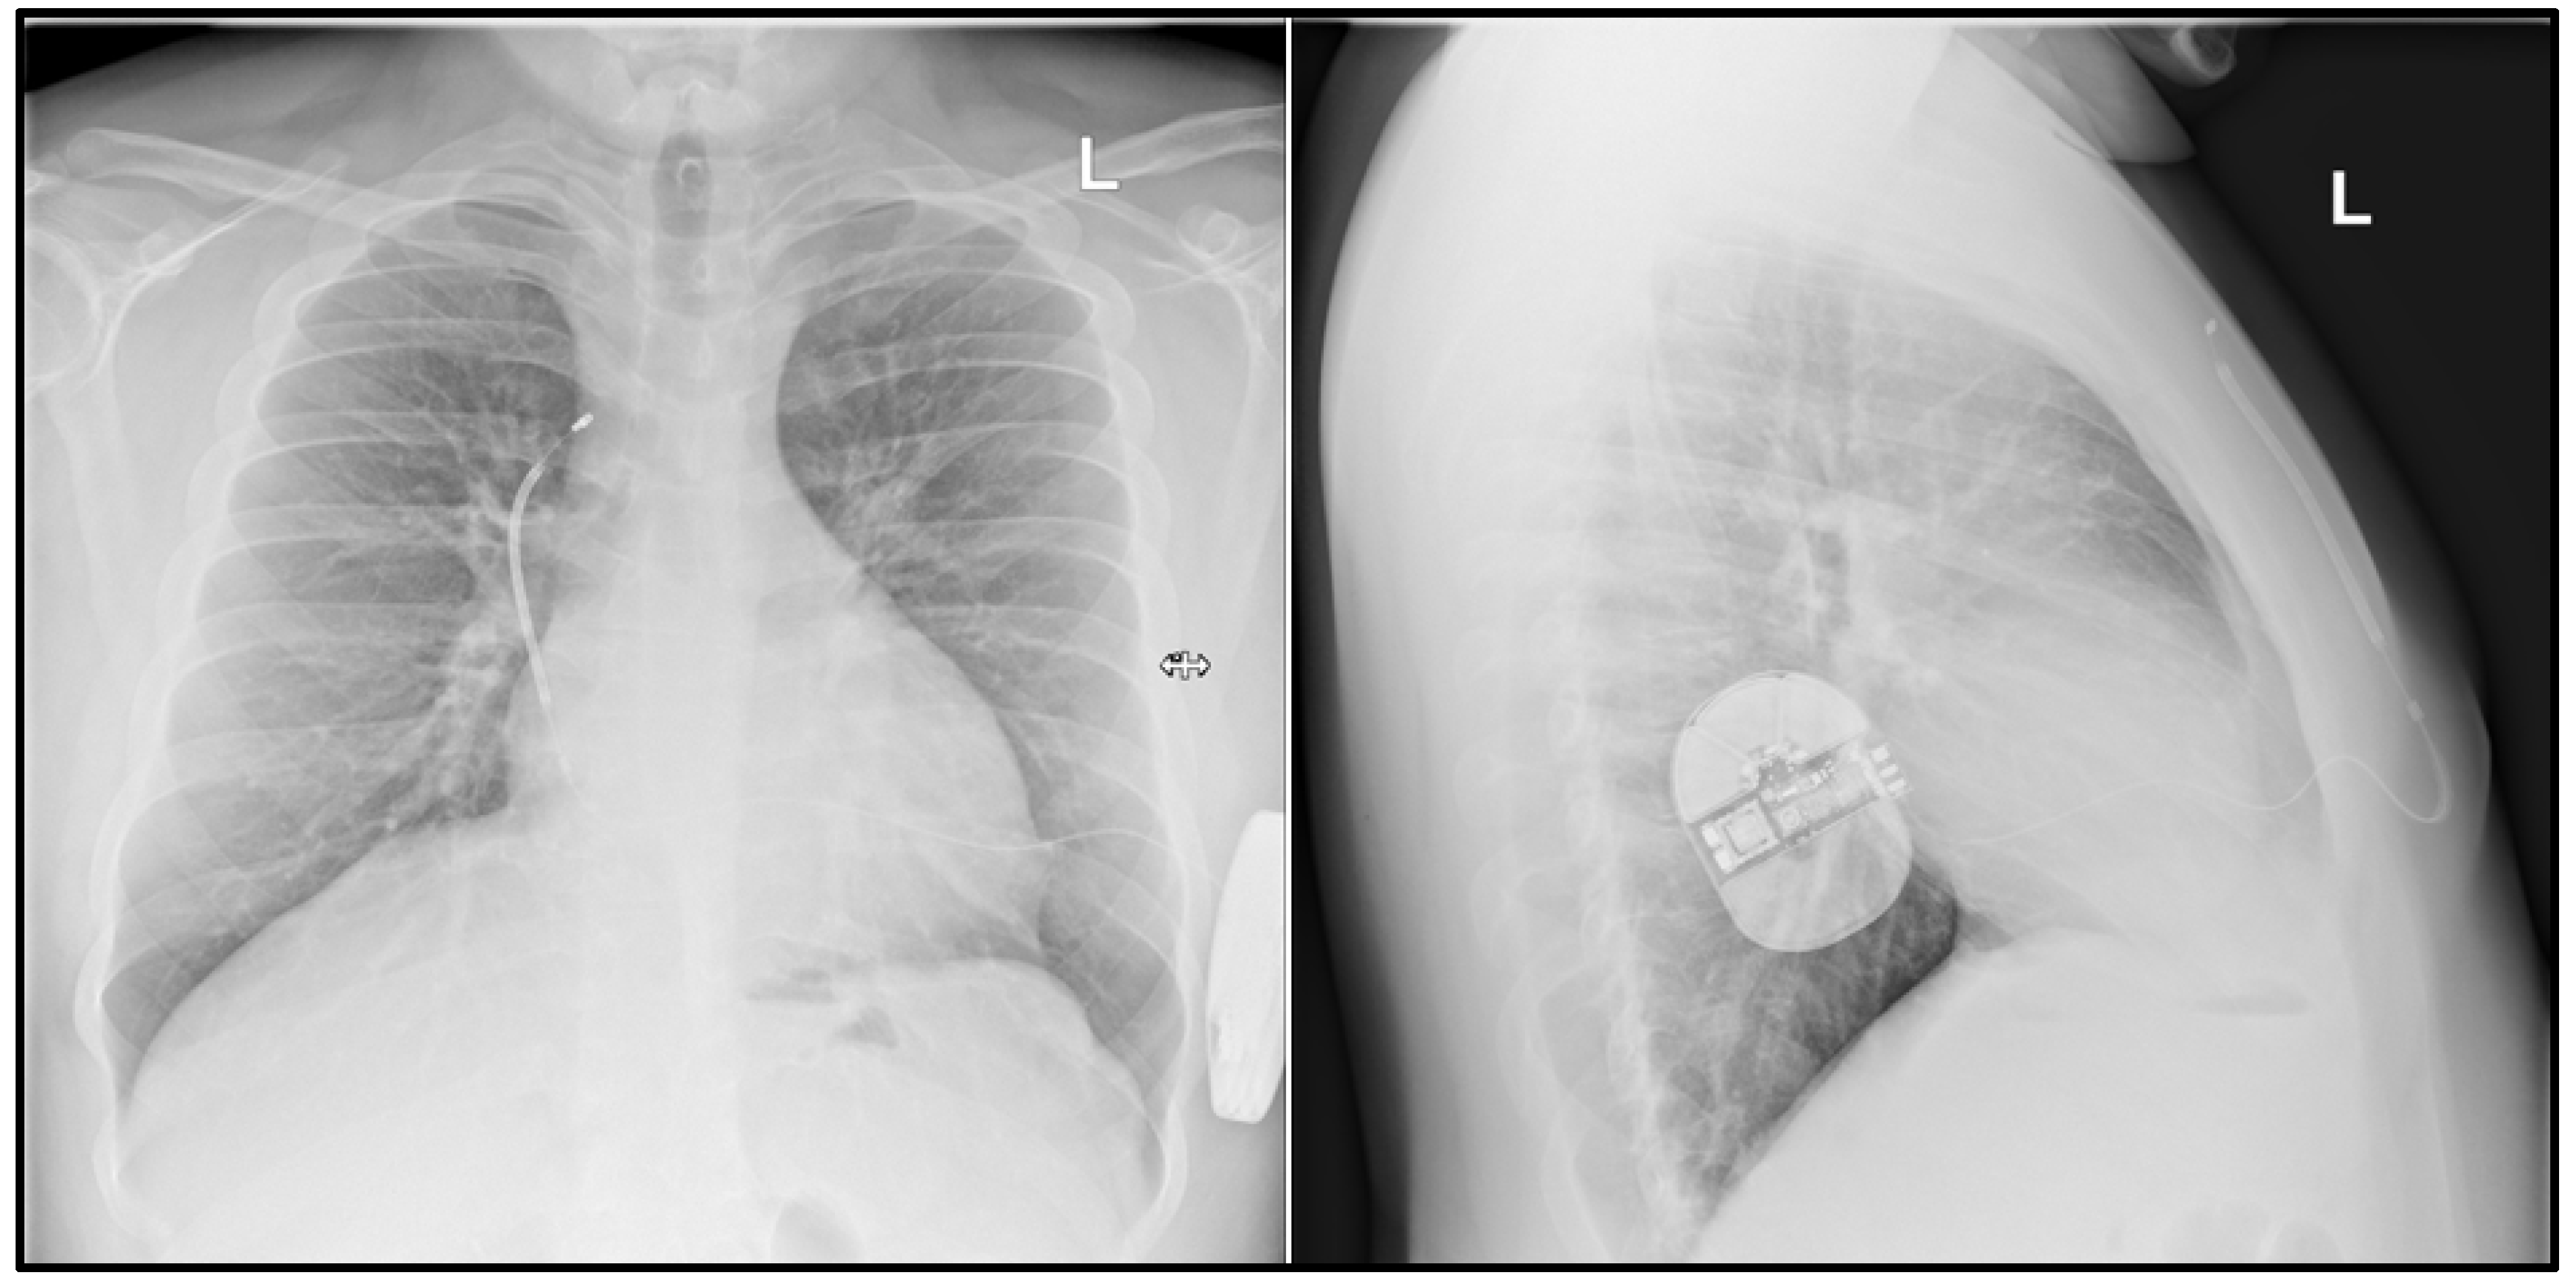

- A 17-year-old male patient with heart failure in the course of dilated cardiomyopathy, with gradually worsening left ventricular function and coexisting complex ventricular arrhythmia (VT episodes up to 170/min) and ventricular tachycardia (VT) with celiac disease, congenital IgA deficiency, and history of renal failure episode. The patient was qualified for heart transplant and LVAD (left ventricular assist device). A HeartMate 3 was implanted for left ventricular support as a bridge for heart transplantation. At the time of publication, the patient has not yet received a heart transplant. He is doing well, helps with lighter household chores, meets with friends, has a girlfriend, and describes his quality of life as satisfactory (Figure 1).